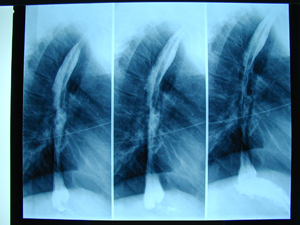

Εικόνα 2 α-γ

Αξονική τομογραφία του θώρακος σε διαφορετικά επίπεδα. Διακρίνεται η παρουσία όγκου στο οπίσθιο μεσοθωράκιο που πιθανά να αποτελεί όγκο του οισοφάγου.